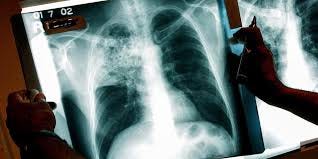

Tuberculosis (TB) is an airborne bacterial infection primarily affecting the lungs. Symptoms can include chest pain, weakness, and coughing up blood or mucus. If left untreated, tuberculosis can be fatal. While it was responsible for a significant portion of deaths in Europe from the 1600s to the 1800s, modern treatment with antibiotics can prevent fatalities.